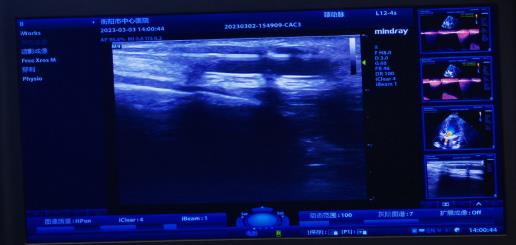

腎內(nèi)科通訊員黃佩君報道:來自衡陽縣的謝奶奶2年前因尿毒癥開始行維持性血液透析維持生命,1周前內(nèi)瘺流量明顯下降,不能滿足透析需要,慕名來到我院腎內(nèi)科就診。彩超檢查提示內(nèi)瘺口至內(nèi)瘺口近心端有約2.5cm管腔狹窄,經(jīng)綜合評估后,腎內(nèi)科陳鐵領(lǐng)副主任、彩超室王勝利副主任醫(yī)師、腎內(nèi)科王靜醫(yī)師給予患者實施彩超引導下動靜脈內(nèi)瘺狹窄球囊擴張術(shù),短短20分鐘便完成手術(shù),術(shù)后患者內(nèi)瘺震顫明顯,流量大幅增加。

動靜脈內(nèi)瘺球囊擴張術(shù)(PTA),通俗地講就是在超聲引導下,通過經(jīng)皮穿刺血管,置入導絲,沿導絲將高壓球囊送至血管狹窄/栓塞病變處,然后使用壓力泵打開球囊,將狹窄/栓塞的病變擴張開的過程。它的優(yōu)勢非常明顯,不僅手術(shù)創(chuàng)面小(無切口,僅為一穿刺點),失血少,安全有效,可反復進行,術(shù)后即可使用,不需中心靜脈靜脈導管過渡,患者舒適無痛苦,最重要的節(jié)省保護了患者的血管資源,可確保透析順利進行。是目前動靜脈內(nèi)瘺狹窄/栓塞首選治療方法。